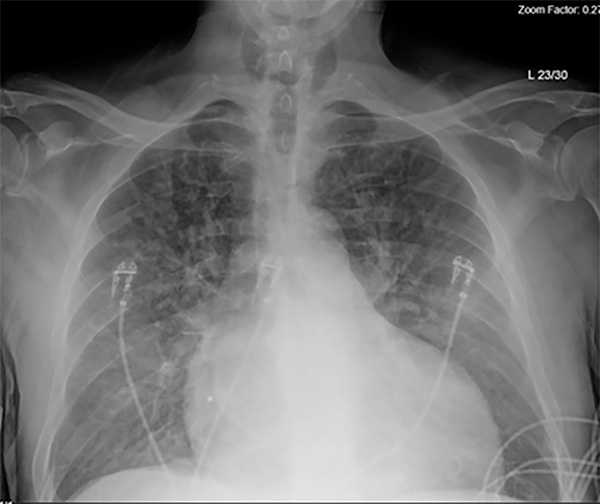

The next aspect of the diagnostic workup includes obtaining a chest radiograph (CXR). (See Figure 1.) The benefits of CXR include its wide availability, low cost, and low radiation exposure. The CXR can be used to aid in diagnosis and assess for signs of pulmonary congestion.6

Figure 1. Chest Radiograph Demonstrating Diffuse Pulmonary Edema in a Patient with Acute Decompensated Heart Failure |

Source: R. Gentry Wilkerson, MD. |

A systematic review and meta-analysis by Wang et al found that a CXR showing signs of pulmonary vascular congestion significantly increased the likelihood of an HF diagnosis in patients presenting to the ED with dyspnea (likelihood ratio [LR], 12.0). They also found that the absence of cardiomegaly and the absence of pulmonary venous congestion on CXR significantly reduced the likelihood of an HF diagnosis (LR, 0.33 and 0.48, respectively). Other findings that reduce the likelihood of HF include the presence of pneumonia or hyperinflation.44 Another study by Mant et al found that any CXR finding associated with HF was 68% sensitive and 83% specific for the diagnosis.45